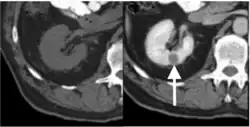

Computed tomography (CT)

Contrast-enhanced computed tomography (CT) is most commonly used to identify the subtypes of RCC. PRCC can be differentiated from other types of RCC due to its distinguishing features, displaying a small hypovascular renal tumor on T2 weighted images.[7] Typically, PRCC tends to appear homogeneous while clear cell RCC is likely to be in a heterogeneous form when the tumor is less than 3 cm in diameter.[30] Comparatively, in cases of tumors larger than 3 cm in diameter, PRCC is generally heterogeneous with areas of necrosis and hemorrhage compared to chromophobe RCC.[8][31] Solid, small PRCC tumors (<3 cm in diameter) are more easily viewed on nephrographic, excretory phase images rather than on unenhanced, corticomedullary phase images.[8]